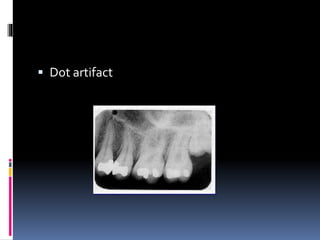

 Dot artifact